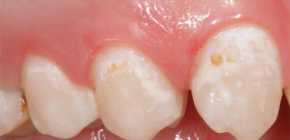

Cárie inicial na fase local e seu tratamento

Antes de se fazer sentir plenamente, a cárie em seu desenvolvimento passa pelo estágio inicial associado à desmineralização gradual do esmalte dentário. Esse processo possui características interessantes e a cárie inicial correspondente é caracterizada por um quadro clínico especial e métodos de diagnóstico. Falaremos sobre o que causa o processo carioso, como ele é tratado no estágio inicial e como podemos nos proteger dele.